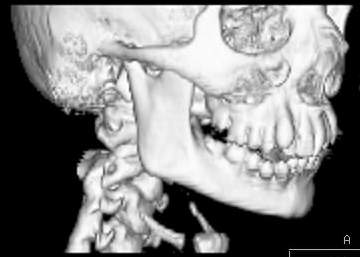

Пациент В., 13 лет. Диагноз: Костный анкилоз левого височно-нижнечелюстного сустава (ВНЧС), левосторонняя микрогения. Болеет с 2-х летнего возраста. Возможная причина развития анкилоза – воспалительный процесс (в первые 1,5 года жизни часто болел простудными заболеваниями, травму родители отрицают). В 3 и 5 лет проводилась редрессация – безуспешно.Прилагаются: ортопантомограмма, кадры СКТ с 3Д реконструкцией. Вопросы: определение тактики лечения – вид и сроки реконструктивно-пластической операции (этапов операции), а именно – неоартропластики и устранения микрогении, медикаментозная терапия в до- и послеоперационный период, ортодонтическое лечение.